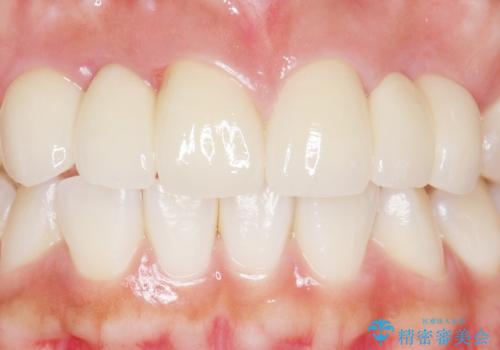

自然な仕上がりにご満足頂けました。

治療終了後、奥歯に残っていた矯正の接着剤を除去し、ホワイトニングも行いました。

クラウンの種類:オールセラミッククラウン スタンダード